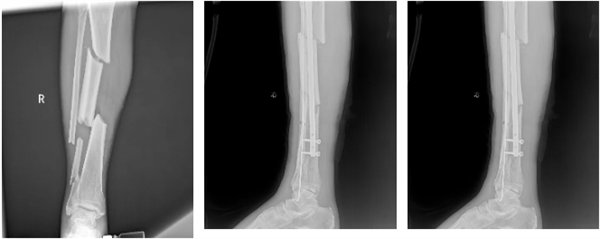

从7月29日的“右侧胫腓骨下端开放性骨折闭合复位内固定术+外固定术”,到9月2日的“右下肢清创术+局部转移皮瓣修复术+取皮植皮术”,再到9月29日的“右胫骨粉碎性骨折闭合复位+有限切开髓内针内固定术”,三次关键手术环环相扣、精准施策。术后,医疗团队持续给予抗感染、消肿止痛、抗凝、促骨折愈合等综合治疗,护理团队则从伤口护理、肢体功能训练到营养支持全程精细化照护,用专业与温暖陪伴患者度过艰难的康复期。